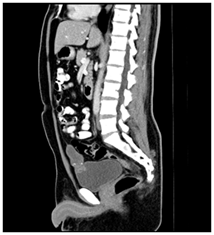

A 41-year-old male patient, who went to the Urology service of the Medical Center Lic. Adolfo Ruiz Cortines (IMSS) by macroscopic hematuria, no clots formation, associated with pain in the hypogastrium. He reported weight loss of 10 kg in three months. Physical examination was observed the abdomen with discrete volume increase in the hypogastrium and palpation a tumor of Approximately 5 cm, depending on the scar umbilical, mobile, not painful or fixed in the deep planes, slightly indurated. Laboratory studies reported cytometry hematics within the normal parameters; blood chemistry with glycemia of 164 mg/dL, urea of ​​40 mg/dL and creatinine 1.1 mg/dL. The general examination of urine with glycosuria, proteinuria, hemoglobin (+) and numerous erythrocytes. The ultrasound abdominal bladder showed a lobed image, of heterogeneous content adjacent to the upper wall. Abdominal-pelvic tomography (Figure 1) and (Figure 2) reported: free retroperitoneum lymphadenopathy, morphology of large vessels with normal diameter and path; in the cavity pelvic urinary bladder was observed with thickening from the wall and in the middle line the wall anterior with irregular, heterogeneous image, which was enhanced with the contrast medium, with towards the abdominal cavity and wall, 38 x 27 mm, with multiple calcifications Punctiform peripherals. (Figure 3) evidenced a tumor in the bladder dome of solid aspect, with zones of brown color, approximate diameter of 3 cm and irregular edges. The treatment consisted of Transurethral resection of the bladder, with results satisfactory.

Figure 2 Contrast Tomography that evidence the tumor, with infiltration in the bladder dome.